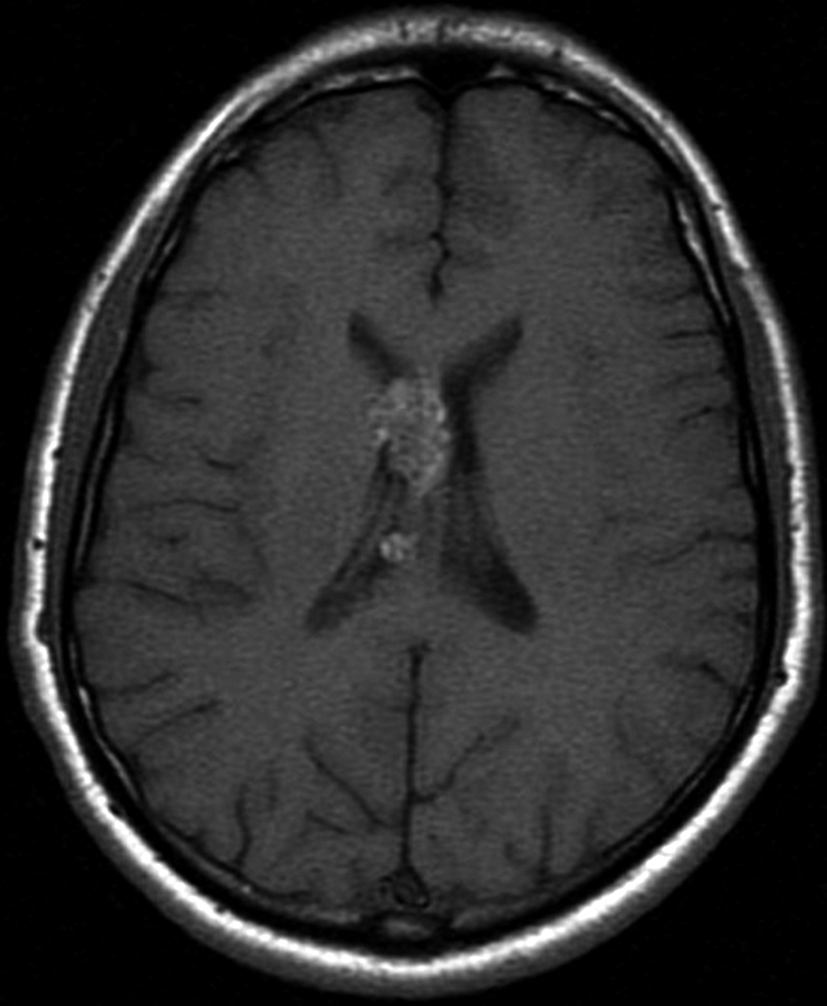

Con los hallazgos tomográficos, no se efectúan planteos diagnósticos y se realiza una resonancia magnética con la finalidad de obtener más datos semiológicos en busca de una aproximación diagnóstica. Se realizó el estudio por medio de secuencias T 1, FSE T 2, FLAIR, SWI y Difusión, en cortes axiales, FSE coronal y sagital T 1. Se realiza la administración de gadolinio DTPA en los tres planos. Se evidencia la lesión bien definida a nivel del ventrículo lateral derecho, que involucra al tronco del cuerpo calloso (Figura 2- C y 3- B). Presenta intensidad de señal heterogénea en secuencias T1 y T2 (Figura 3 y Figura 4). En secuencia ecogradiente se observa una señal marcadamente hipointensa y heterogénea, con un halo hipointenso bien definido (Figura 2- C). No presenta realce significativo tras la administración de Gadolinio (Figura 2- B) y en la secuencia de difusión no presenta restricción.

Figura 2 Resonancia magnética.

a) Imagen axial T1, lesión intraventricular con intensidad de señal heterogénea.

b) Tras la administración de Gadolinio no presenta realce significativo.

c) Imagen axial en secuencia ecogradiente donde se evidencia la lesión hipointensa y heterogénea. Se observa la extensión de la lesión al cuerpo calloso.